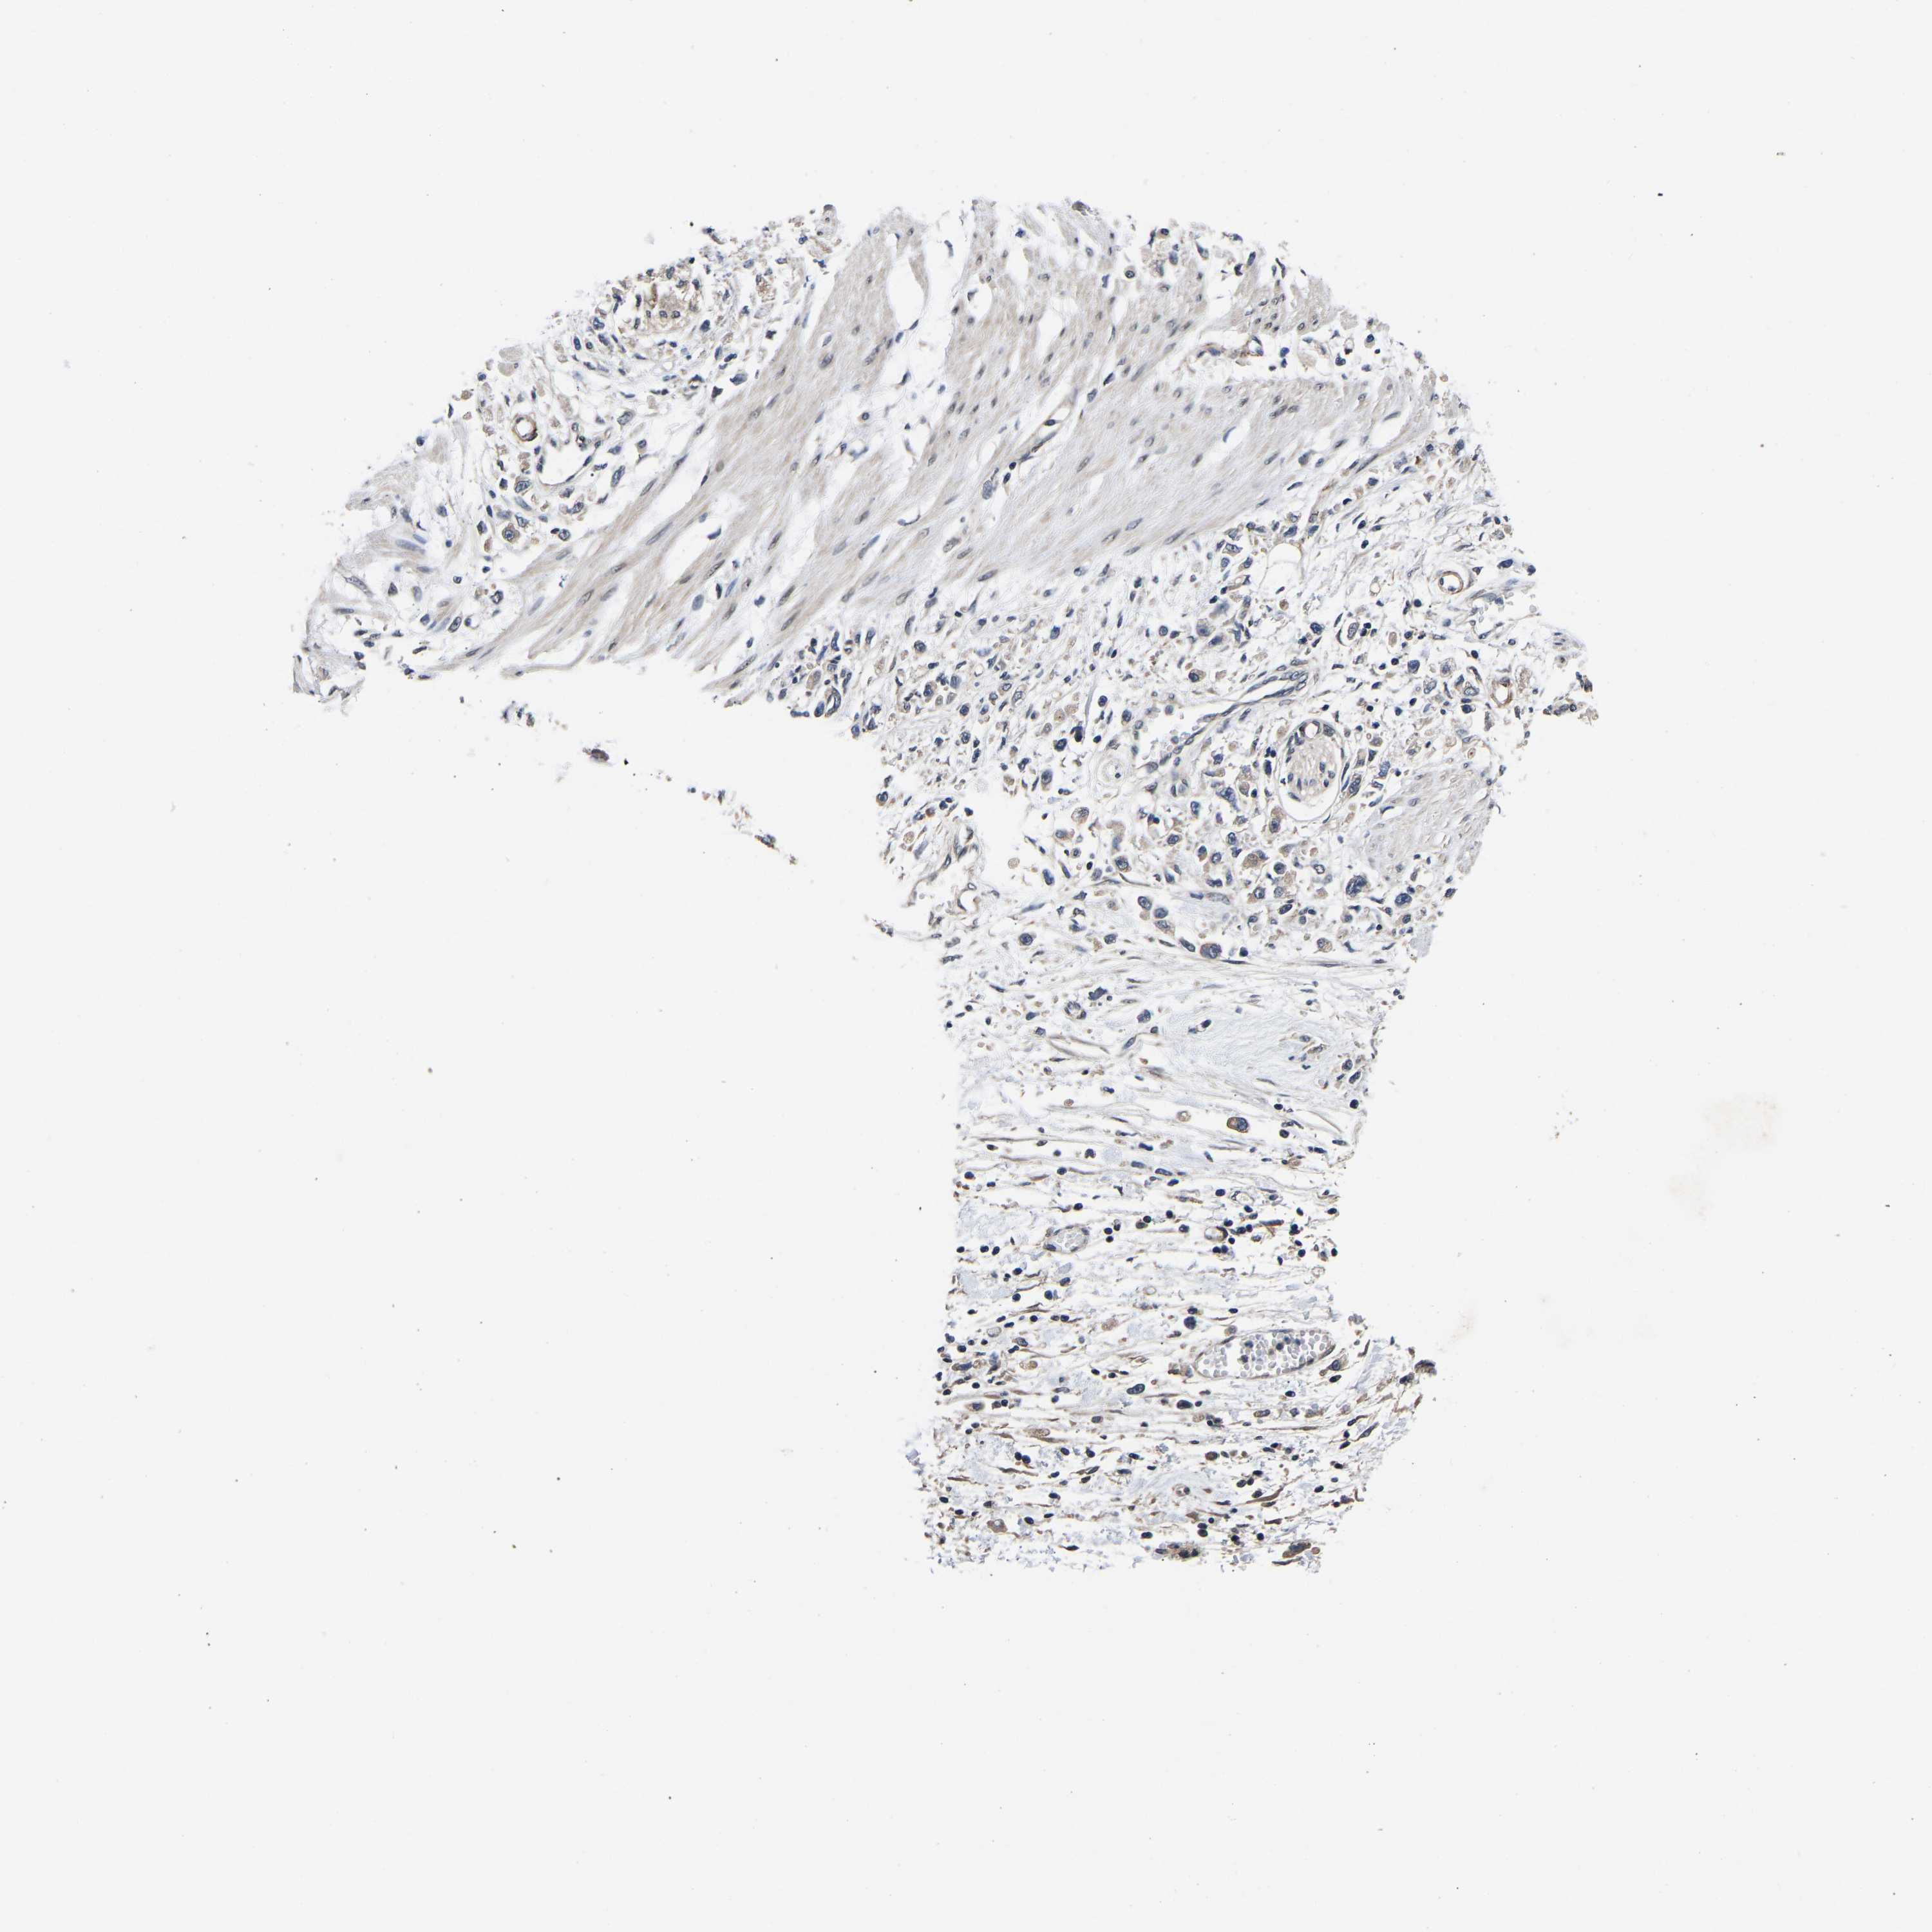

STOMACH CANCER - Protein expressioni

A mouse-over function shows sample information and annotation data. Click on an image to view it in a full screen mode. Samples can be filtered based on level of antibody staining by selecting one or several of the following categories: high, medium, low and not detected. The assay and annotation is described here.

Antibody stainingi

Antibody staining in the annotated cell types in the current human tissue is reported as not detected, low, medium, or high, based on conventional immunohistochemistry profiling in selected tissues. This score is based on the combination of the staining intensity and fraction of stained cells.

Each image is clickable and will lead to virtual microscopy that enables deeper exploration of all samples and also displays staining intensity scores, fraction scores and subcellular localization as well as patient and tissue information for each sample.

Antibody HPA020352

Staining

High

Medium

Low

Not detected

Intensity

Strong

Moderate

Weak

Negative

Quantity

>75%

75%-25%

<25%

None

Location

Nuclear

Cytoplasmic/membranous

Cytoplasmic/membranous,nuclear

Adenocarcinoma, NOS